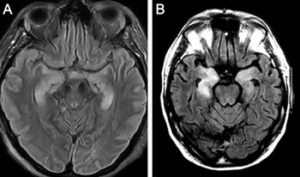

A Rare Case of Autoimmune Encephalitis: Diagnosis and Management August 25, 2024 No Comments Autoimmune encephalitis (AE) is a complex and often challenging condition to diagnose and manage. It involves inflammation of the brain caused by